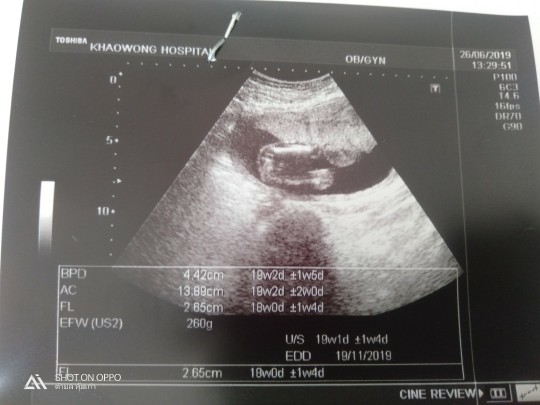

แบบนี้ หญิงหรือชายค่ะ

ชายค่ะ ปิกะจูชัดมาก